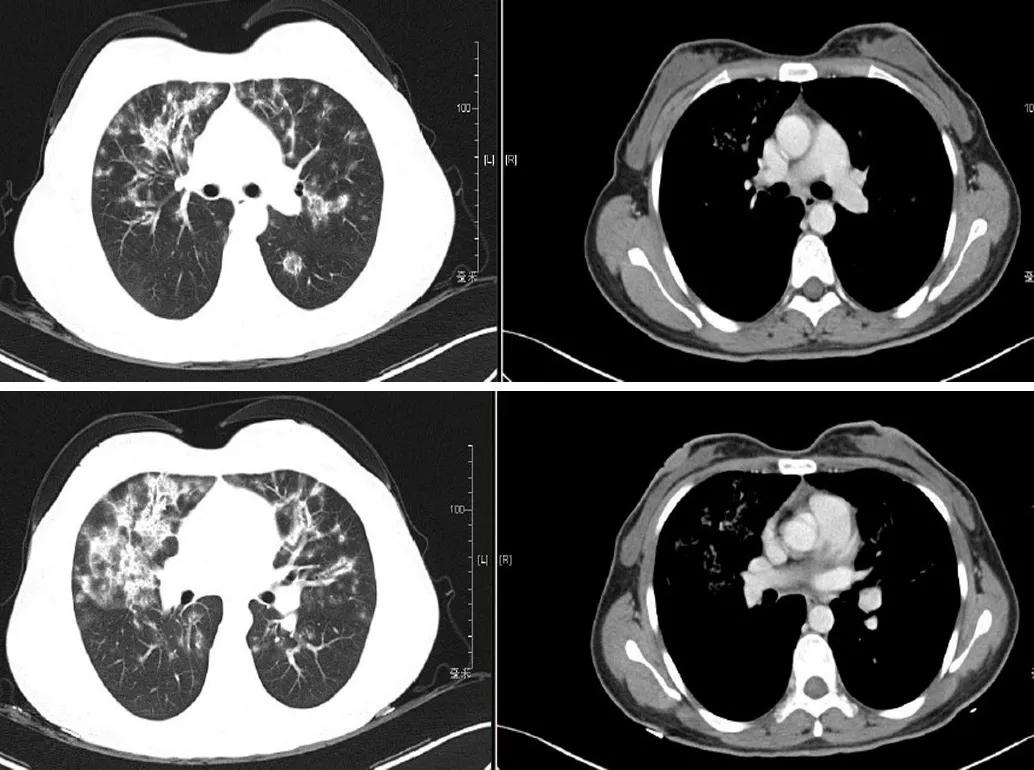

入院时胸部CT:

患者青年女性,急性起病,临床症状主要为咳嗽、气促,胸骨后疼痛,无发热、咯血、低热,血常规、炎性指标正常,胸部影像学见双肺弥漫性病变,经抗生素抗感染后病情无改善。需要考虑社区获得性肺炎(CAP)、病毒性肺炎和机化性肺炎(OP)等疾病。该患者符合社区发病,有新出现的咳嗽气促,胸部CT有新出现的斑片浸润影,符合社区获得性肺炎的初步诊断。但经验性抗感染治疗后影像学有加重,需进一步排除肺结核、肿瘤、间质性病变等的可能。社区获得性肺炎常见病原体包括细菌、非典型病原体、军团菌,初始治疗已经覆盖,但影像学仍有进展,结合病毒性肺炎影像学也可表现为两肺多发的磨玻璃实变影,故需进一步排查有无病毒性肺炎。机化性肺炎分为SOP和COP。SOP多继发于肿瘤、感染或结缔组织病相关性疾病等。该患者目前无明确肿瘤疾病,无发热脱发、皮疹、关节疼痛等症状,自身抗体阴性,炎性指标正常,故SOP的可能性不大。COP患者一般有发热、气促、干咳等,经抗感染治疗无好转,影像学可表现为下叶、外周、胸膜下多发的磨玻璃实变影,可有反晕征,游走性,该患者需考虑COP的可能。

侯医生读片还是很全面的,但读片更应该结合病史。该患者青年女性,急性起病,胸部影像提示双肺弥漫性病变,读片时应关注累及的部位,是实质还是间质、血管等。此片目前未见胸水,胸膜未累及;再看分布,两肺弥漫性分布,沿着支气管血管束,肺血管疾病基本可排除。病灶性质,磨玻璃改变,支气管壁增厚,形成牵拉性支扩,有间质累及。同时有实变,存在反晕征,结节样改变,根据影像缩小诊断范围。结合该患者影像特点,首先考虑吸入性问题,是否有慢性过敏性肺炎可能,但病史上无反复发热,反复疾病发作的情况,暂不考虑。另外还需要考虑肺曲霉病,但患者无相关暴露史,无免疫抑制基础,暂不考虑肺曲霉病。结节病和机化性肺炎也存在类似的影像学改变。其他的如急性间质性肺炎和淋巴瘤,也需要进一步鉴别。沿支气管血管束分布的还有卡伯氏肉瘤,可根据免疫细胞、HIV等后续的辅助检查进行鉴别诊断。